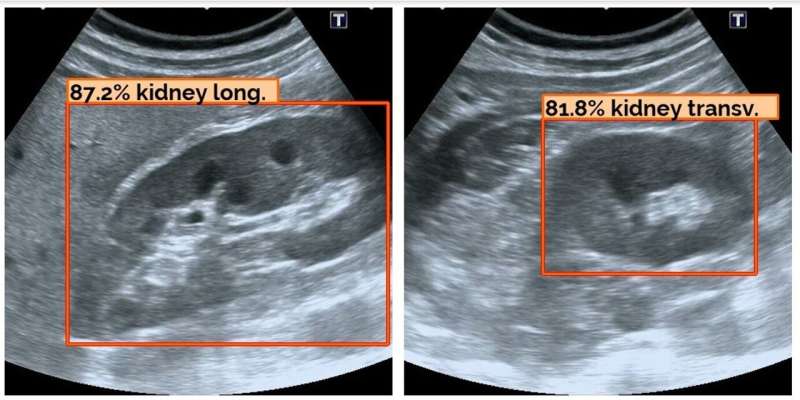

ALISSE able to differentiate between the clinically valuable long ways ‘plane detection mode’ for an organ versus a less useful ‘transverse’ side view. Credit: ALISSE consortium

However ALISSE users receive detailed guidance of where in the body to place the ultrasound wand, are provided with example images of the target organ and given the percentage likelihood of the object in view being the correct target. The system is also able to differentiate between the clinically valuable long ways "plane detection mode" for an organ versus a less useful "transverse" side view.